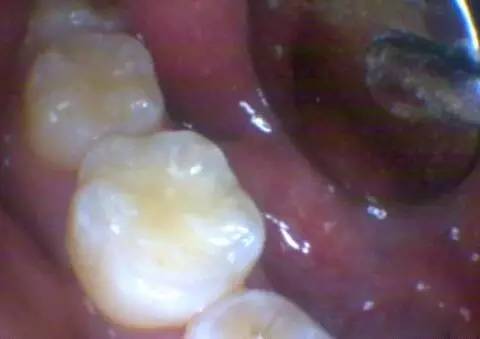

现在再来看看另一个病例,补牙之前的口内照片,没有大的龋洞。

橡皮障下去除表面腐质后,里面的深洞及深部的龋坏组织。

是不是觉得有点吃惊?腐质去除干净后的样子。

——原来有这么深啊!